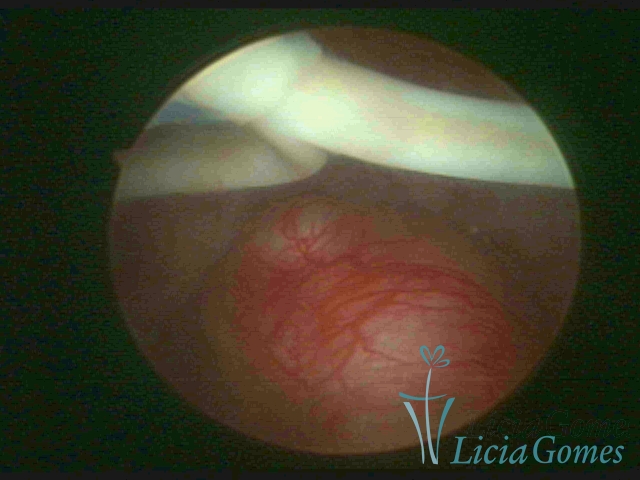

Mirena and myoma

×